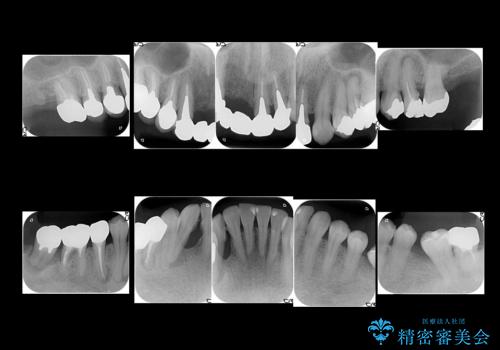

- 全体的な虫歯治療、根管治療、および歯周病治療を行いました。

歯周病治療につきましては歯周ポケット除去のために歯周外科処置(APF)を行っています。

左下6の欠損については左下7はワイヤー部分矯正でアップライトを行い、補綴スペースを確保しています。

右下犬歯は歯周病の進行が重度のため、やむなく抜歯をし、骨増生後にインプラント埋入を行っています。

根管治療は横浜桜木町歯科 大元先生が担当しました。

右下7の根管治療および再植は銀座院 林先生が担当しています。(抜歯は希望されなかったため、再植を行い、現在経過観察中です。)